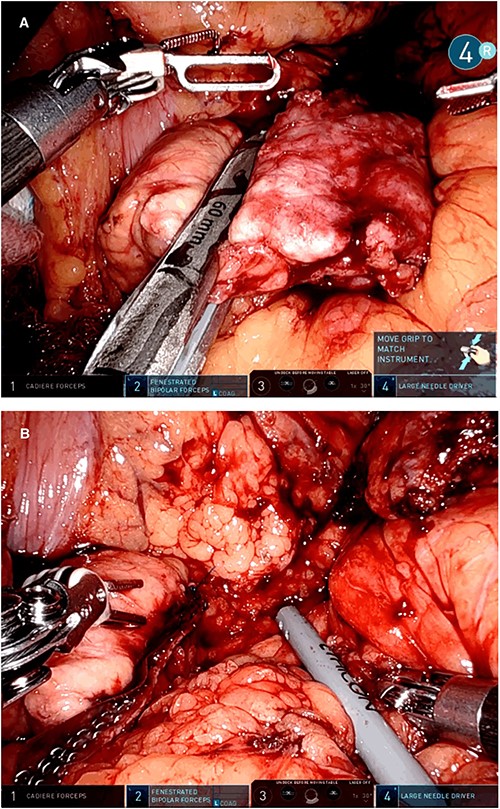

A robotic redo distal pancreatectomy was performed. Adhesions from the previous operation were taken down and the pancreatic stump was dissected. Samples of lymphatic tissue were sent for permanent pathology. An intraoperative ultrasound scan was done to localize the tumor and rule out concomitant lesions. A 2-cm nodule was found in the pancreatic stump (Fig. 3). With precise dissection, the gland was mobilized, reaching the confluence of the splenic and the portal vein. Afterward, the pancreatic stump was resected using a linear stapler (Fig. 4A and B). Once hemostasis was obtained, fibrin glue was applied to the section line and two drains were left close to the stump (Fig. 5). The patient was discharged on postoperative day 7. She developed a pancreatic biochemical leak that was managed conservatively. The histopathology analysis showed a grade 2, 1.3 cm well-differentiated neuroendocrine tumor with a low mitotic rate and Ki 67 index of 3%. After 16 months of follow-up, there was no evidence of recurrence.

Intraoperative picture showing the pancreatic resection with a linear stapler (A) and the pancreatic stump with the stapler reinforcements in the resection line (B).